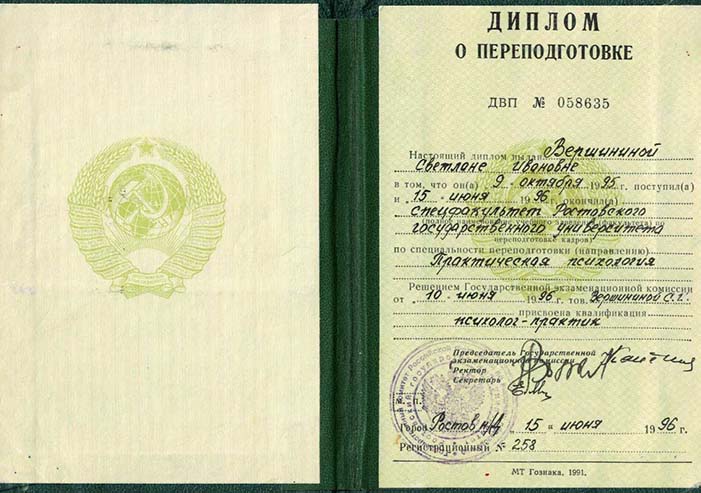

Лицензии и сертификаты нашей клиники

Медицинские услуги оказываются ООО "ЮгЭкоСервис+" по лицензии ЛО-61-01-008143 от 28.12.2021 г.